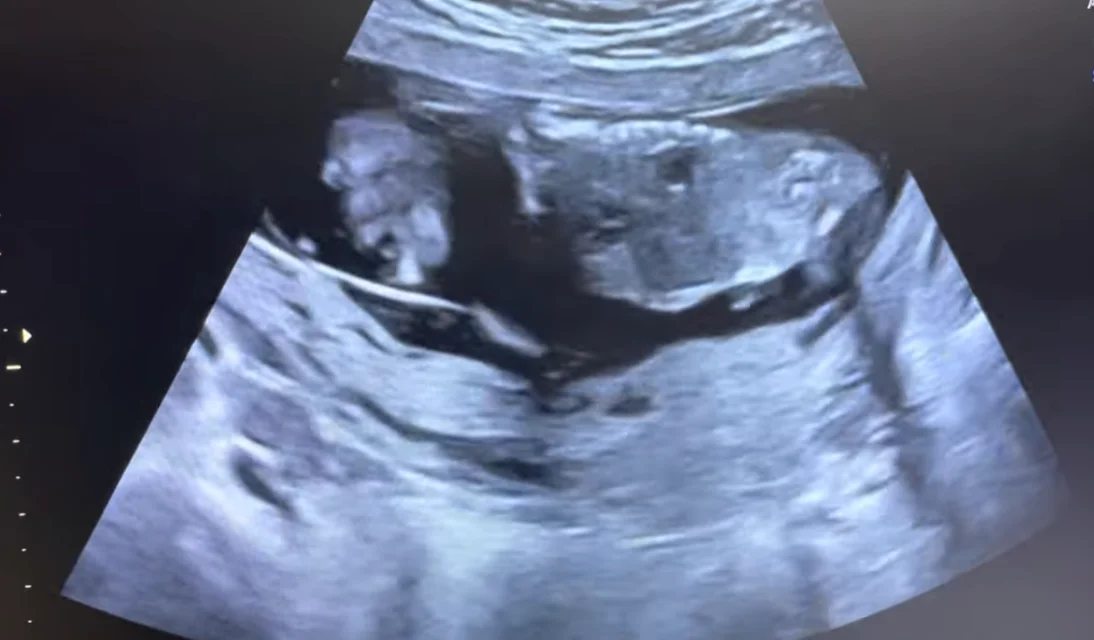

Dây rốn thắt nút (True Umbilical Cord Knot)